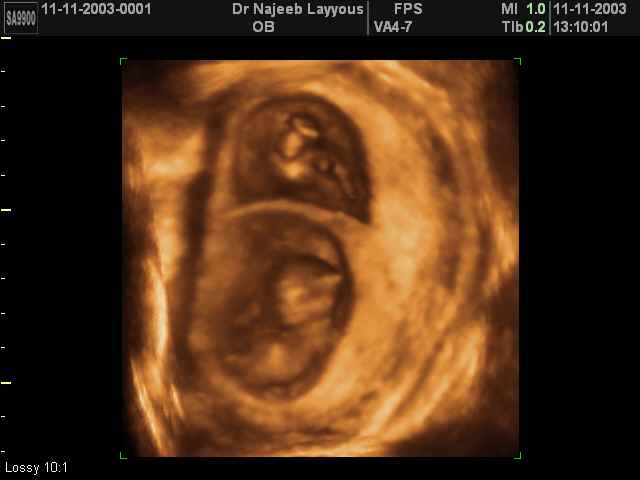

- 3D Photos échographie de grossesse multiple

3D Photos échographie de grossesse multiple : Jumeaux, triplés et quadruples| Dr N Layyous